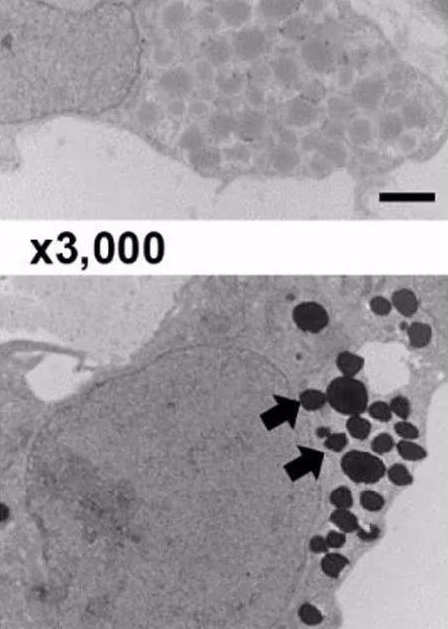

圖. 電鏡下細胞內EPO的分泌囊泡